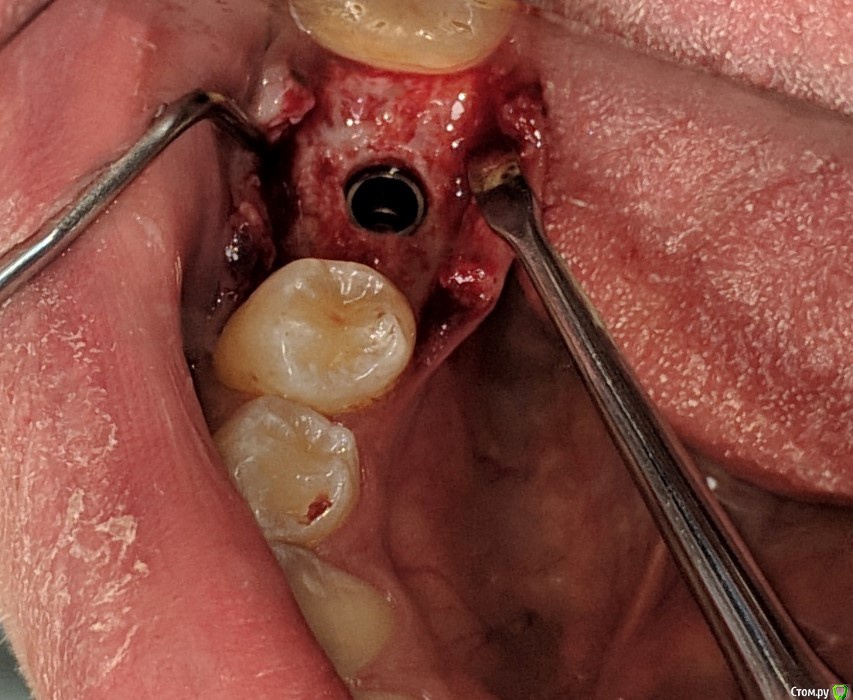

MP1121 Опубликовано 4 августа, 2020 Автор Поделиться Опубликовано 4 августа, 2020 Понимаю) пПциент, позвонил мне после консультации ортопеда в другой клинике, спросил почему ему даже не предложили костную пластику. Ну думаю ок, пациент что-то напутал, бывает, успокоил, попросил номер врача, созвонился и в ответ тоже самое... Я сказал что вестибулярно от шейки импланта кости миллиметра 3, и над платформой 4-5 мм. десны. Предложил узнать мнение коллег и дать ему ссылку на форум. КТ после операции не делали, но сейчас хочу направить.Не претендую на звание виртуозного хирурга, да и практикую всего два года, но такая ситуация очень неприятна. Ссылка на комментарий

колесников Опубликовано 5 августа, 2020 Поделиться Опубликовано 5 августа, 2020 Ортопед оценивает с учетом будущей реставрации. Относительно моляра есть дефицит объёма гребня,но для имплантации объём костной ткани достаточный. Данный дефицит нивелируется дополнительной пластикой мягких тканей вестибулярно и земной с узкого на широкий фдм. Но мне кажется ,вы слишком язычно сместили платформу , и теперь решить проблему заменой на более широкий но стандартный фдм ,будет не просто,придётся делать индивидуальный. 1 Ссылка на комментарий

колесников Опубликовано 6 августа, 2020 Поделиться Опубликовано 6 августа, 2020 Спасибо! А можно ли решить вопрос временной коронкой? Возможно в два этапа (постепенно добавляя объем вестибулярно композитом) Времянки буду делать сам определенно лучше делать через временную. Рентген бы не помешал,на каком уровне платформа?. Хорошо если вы делали редукцию гребня у платформы. Можно и за один раз ,но подсечь и сместить лоскут вестибулярно. 1 Ссылка на комментарий

MP1121 Опубликовано 7 августа, 2020 Автор Поделиться Опубликовано 7 августа, 2020 определенно лучше делать через временную. Рентген бы не помешал,на каком уровне платформа?. Хорошо если вы делали редукцию гребня у платформы. Можно и за один раз ,но подсечь и сместить лоскут вестибулярно.Спасибо. Редукцию не делал, имплант (anyone) немного заглубил где-то на 1 мм. А подсечь это как? Или имели ввиду рассечь? Ссылка на комментарий